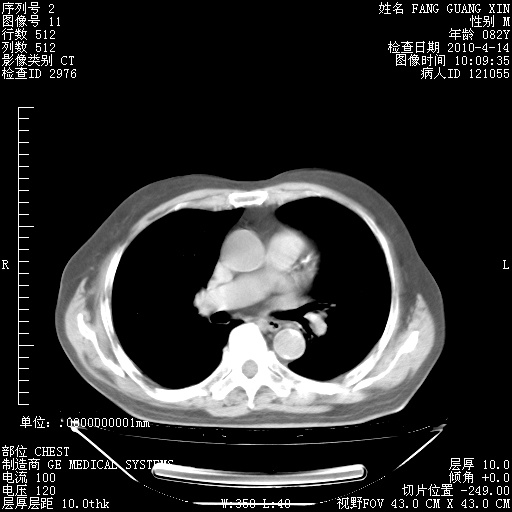

4月28日肺部CT——再次出现类似去年5月9日——透光度降低,(影像科认为)“间质性”改变。

1221483 1 .bmp

1221483 2 .bmp

1221483 3 .bmp

1221483 4 .bmp

1221483 5 .bmp

4月28日肺部CT——再次出现类似去年5月9日——透光度降低,“间质性”改变。